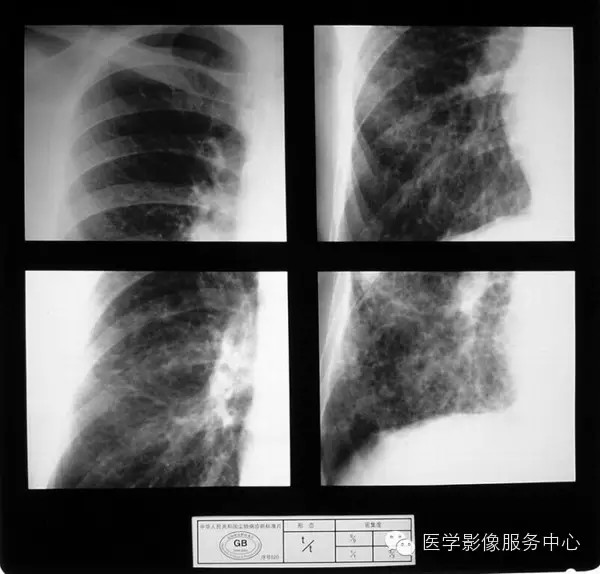

4.4 三期尘肺(Ⅲ)

a)Ⅲ:有大阴影出现,其长径不小于20mm,短径不小于10mm。

b)Ⅲ :单个大阴影的面积或多个大阴影面积的总和超过右上肺区面积者。